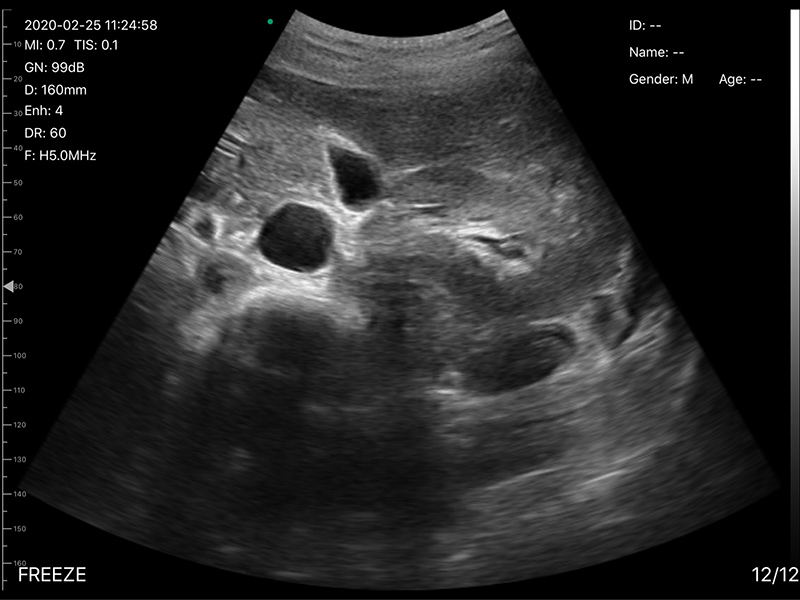

• 探头频率:3.2/5.0MHz

• 扫描深度:90/160/220/305mm,可调

• 图像调节:增益、焦点、反相脉冲谐波、降噪